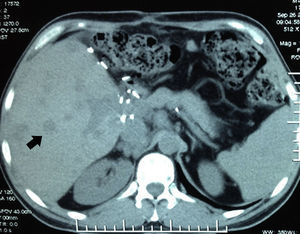

Inicia su padecimiento en marzo del 2012 con dolor abdominal intenso en epigastrio que posteriormente se generalizo a todo el abdomen; presentó inestabilidad hemodinámica por lo que acudió al hospital en Houston, Texas, EE. UU. (lugar de residencia en ese periodo), donde se diagnosticó sangrado masivo intraabdominal secundario a hemangioma cavernoso de afectación bilobular (fig. 1); se realizó embolización por angiografía, cediendo el sangrado. Posterior a su recuperación se realizó trasplante hepático ortotópico, con compatibilidad sanguínea, de lóbulo derecho, con reconstrucción quirúrgica estándar de donador vivo relacionado en mayo del 2012, en hospital privado en la ciudad de Guadalajara, Jalisco. Serología positiva para citomegalovirus IgG tanto para el donador como el receptor. Es egresado a los 8 días del posquirúrgico con esquema de inmunosupresión a base de tacrolimus, ácido micofenólico y prednisona.

Tomografía axial computada abdominal con contraste oral e intravenoso en fase arterial que muestra líquido libre en cavidad abdominal, de predominio perihepático y periesplénico (flechas negras) así como una lesión redondeada, heterogénea a la captación de medio de contraste que ocupa prácticamente la totalidad del hígado (flecha blanca).